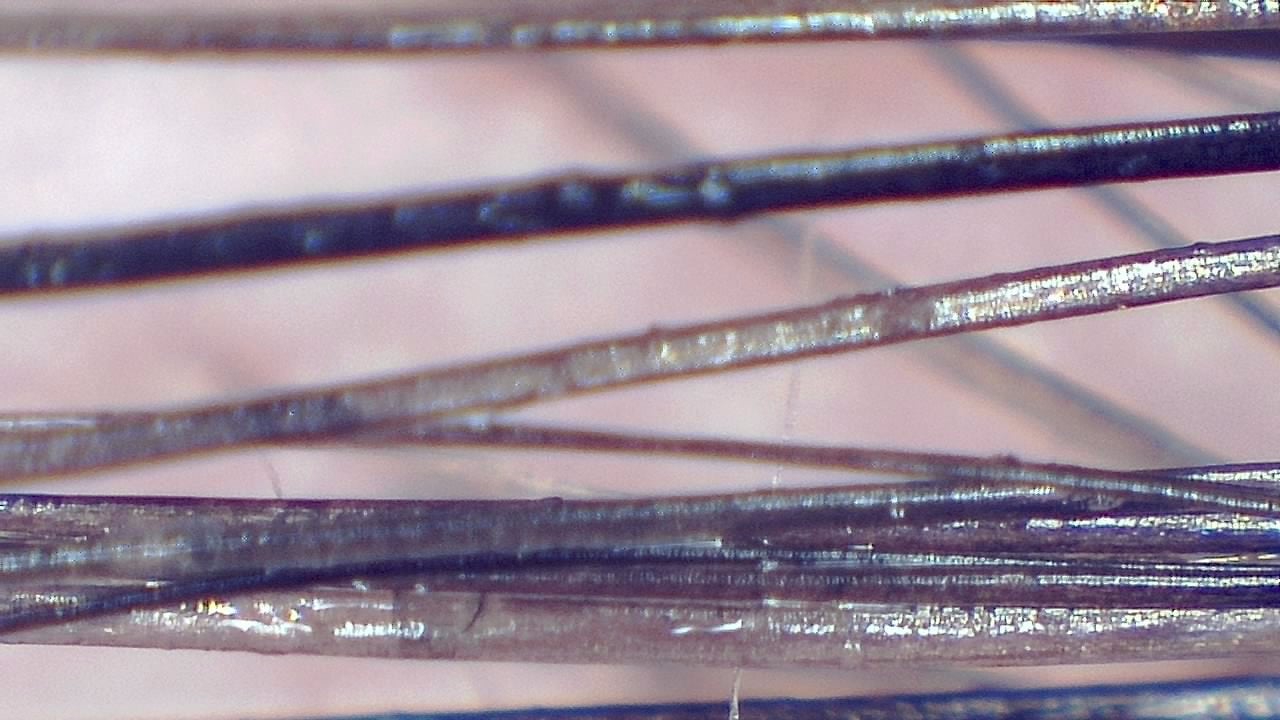

Portable magnified viewing for scalp surface, hair shafts, follicular openings, and visual documentation over time.

Trichoscopy is a non-invasive visual examination technique used by trained professionals to observe the scalp surface and hair shafts. Smart G-Scope provides a portable USB workflow for magnified viewing and image capture.

The device can support documentation of hair shaft appearance, scalp surface features, follicular openings, and visible changes over time. It is most useful when images are captured under consistent lighting and positioning.

What you can observe

- Hair shafts and visible shaft diameter variation.

- Magnified viewing of hair shafts, scalp surface, and visible follicular openings.